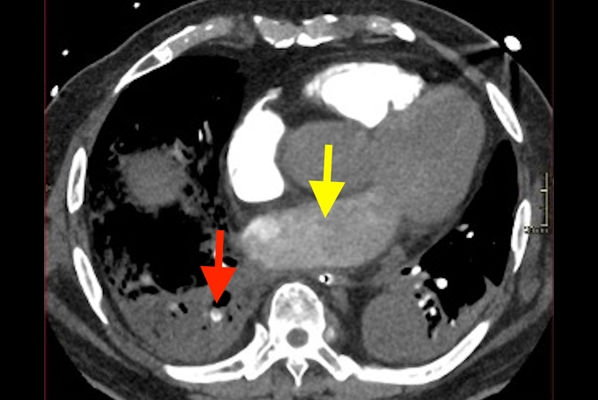

With the emergence of multislice CT scanners, multiplanar reformats were found to be superior for imaging cervical spine trauma compared with plain x-rays. There was increasing recognition of CT scans providing much superior information for body trauma, chest injury with pneumothorax, abdominal injury to the liver, splenic laceration, pelvic viscera, and other conditions. The rapid advances in CT scanning, including thinner slices, were recognized as being essential for emergency medical practice, both for acute abdomen and head and body trauma.

To avoid negative or unnecessary operations, surgeons were increasingly unwilling to take patients for exploratory laparotomies without a CT scan to give provisional or tentative diagnoses prior to surgical exploration. Complex imaging with CT required trained radiologists, rather than emergency physicians or surgeons, to report these images.